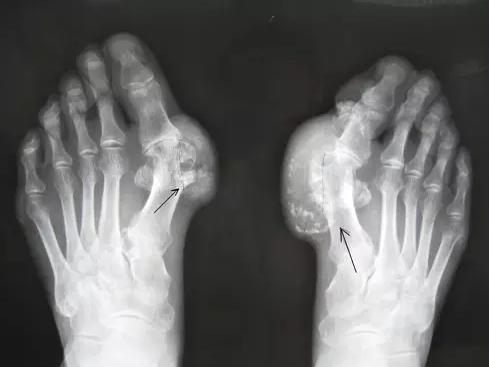

痛风性关节炎和类风湿的区别有哪些?类风湿性关节炎与痛风性关节炎是截然不同的两种疾病,二者无论是在病因、临床表现、实验室检查结果及治疗方法上,均有明显的区别。由于类风湿关节炎也常发生于手指、足趾等小关节,发作时也以疼痛、肿胀、活动障碍等表现为主,病程较久者也会造成关节畸形与破坏,在急性发作时又可伴有发热、全身不适等症状,故常易与痛风性关节炎,尤其是慢性痛风性关节炎型混淆而造成误诊。因此,病人对这两种不同性质的关节炎各自的特点与区别,应有一个概括的了解。

痛风性关节炎和类风湿的区别有哪些?类风湿性关节炎病人在关节周围,尤其是关节隆突部位及经常受压处(例如肘关节的鹰嘴突)可出现类风湿结节,这种结节性质与痛风结节完全不同。它在经过治疗后可完全消失。在实验室检查方面,类风湿性关节炎病人,血中可以查到类风湿因子,血液免疫学检查也可发现不正常。例如血补体c3可降低、冷球蛋白升高,血浆蛋白电泳早期α2增加,慢性期γ球蛋白升高。血尿酸及24小时尿中尿酸测定则正常。贵阳强直医院治痛风